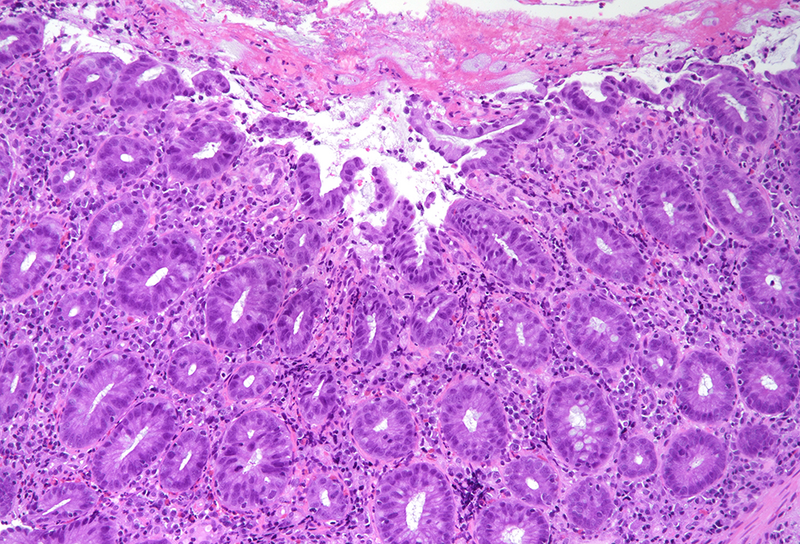

Histology revealed colonic mucosa with preserved architecture. Multiple erosions, crypts with degenerative features and increase of the inflammatory cell infiltrate in the lamina propria, especially granulocytes, were observed (PANEL A-B). On the luminal surface, accompanied by fibrin and debris, multiple organisms with roundish shape, foamy cytoplasm and round, pale and eccentric nuclei were found; some of those have erythrocytes engulfed in their cytoplasm (PANEL C-D); periodic acid-Shiff (PAS) stain highlights these organisms (PANEL E-F), which qualify for diagnosis of amoebiasis.

Histologically, initial lesions show a mild neutrophilic infiltrate, with numerous organisms present at the luminal surface associated with detritus. In advanced disease, ulcers are often deep, extending into the submucosa, sometimes with invasive amoebae within the bowel wall. Entamoeba histolytica has a roundish shape, with foamy cytoplasm and round, pale and eccentric nuclei with an open nuclear chromatin pattern. Within the inflammatory exudate, they may be difficult to distinguish from macrophages; in these cases, histochemical and immunohistochemical stains may be performed: amoebae are trichrome- and PAS-positive and macrophages stain with CD68. It is noteworthy the presence of ingested erythrocytes as pathognomonic feature of this parasite.